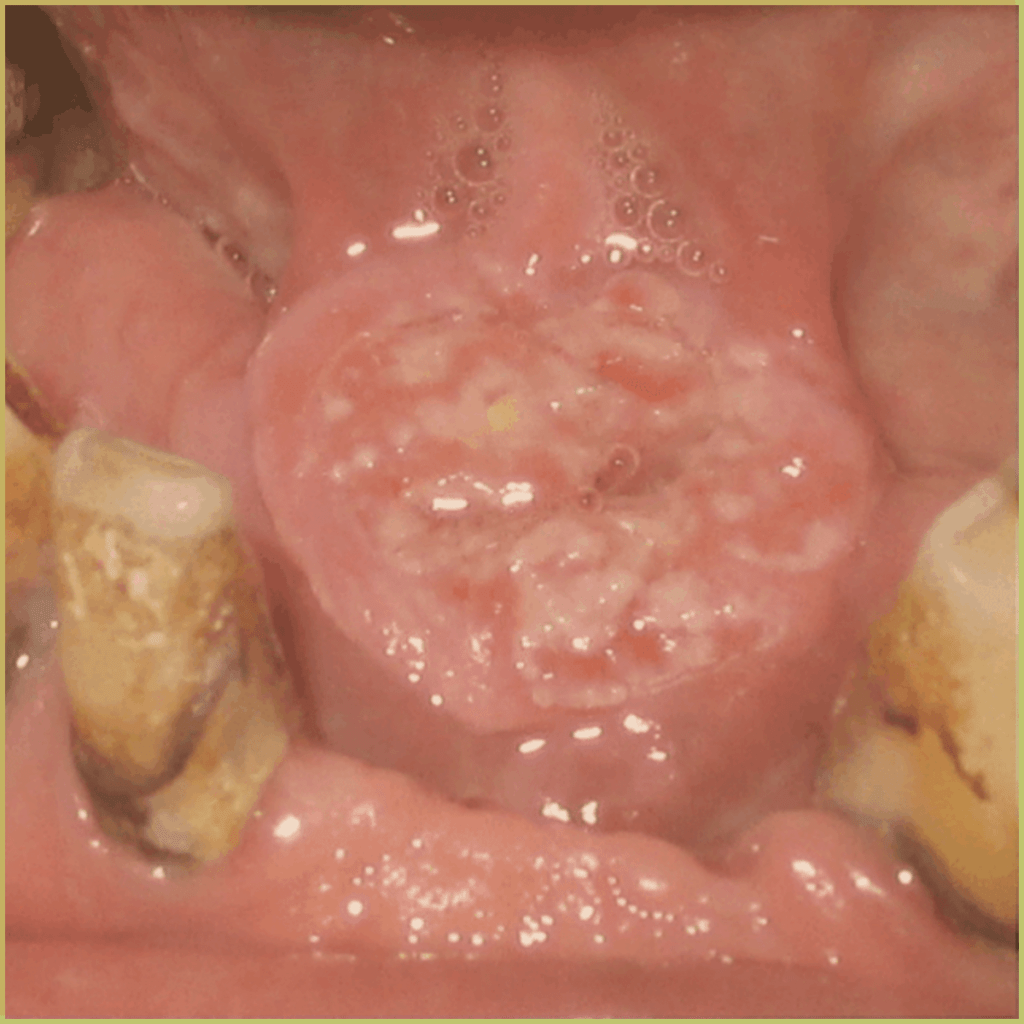

SYPHILIS

Syphilis is a sexually transmitted infection caused by the helically coiled spirochaete bacterium Treponema pallidum. It may also be transmitted from a mother to her child during pregnancy or at birth, resulting in congenital syphilis. There are four stages of infection (primary, secondary, tertiary and latent) and symptoms may vary accordingly. The common clinical presentation includes:

Tertiary syphilis:

- Develops 3 to 10 years after initial untreated lesion.

- Atrophic glossitis with leukoplakia-like features.

- Painless gumma (often large, destructive, solitary granulomatous ulcer) commonly seen on the midline of the tongue or palate.

Congenital syphilis:

- Presents with the Hutchinson’s triad: interstitial keratitis, malformed teeth (Hutchinson incisors and mulberry molars), and eighth nerve deafness.

Diagnosis is based on the lesion history, clinical presentation, serological and direct fluorescent antibody studies, and microscopic findings which may include:

- Positive result using dark field microscopy of serous fluid from a chancre.

- Abundant spirochetes embedded within a mixed cellular inflammatory infiltrate.

Since the condition exists in many variations, your differential diagnosis should include:

- Viral infections (measles, rubella, mononucleosis).

- Deep fungal infection.

- Kawasaki disease.

- Traumatic ulcer

- Squamous cell carcinoma.

- Leukoplakia.

- Midline granuloma.

- Condyloma acuminata.

- Genital warts.

- Herpes simplex, herpes zoster.

Treatment options include:

- Parenteral penicillin or ceftriaxone.

- Oral tetracycline or doxycycline.